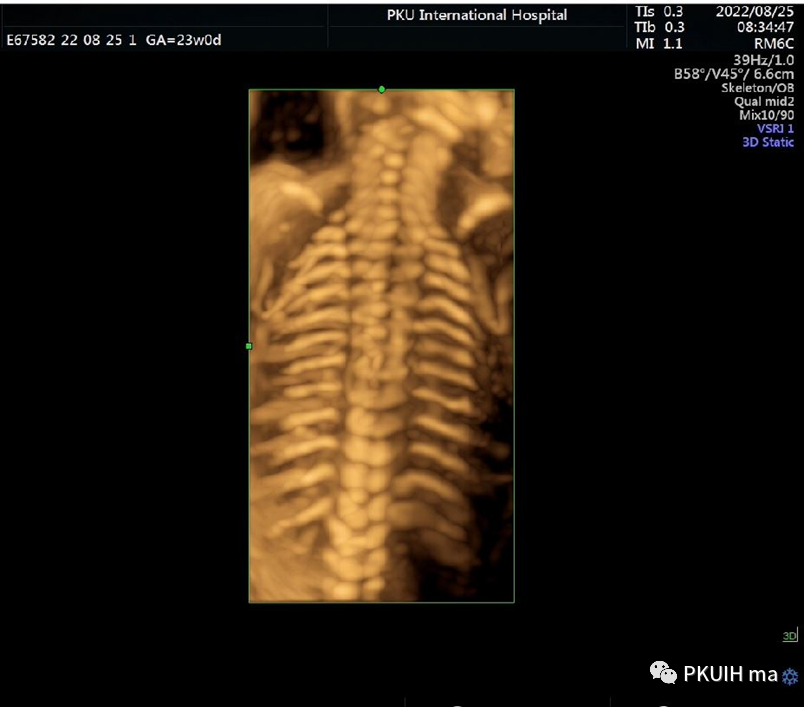

同样对于23周筛畸时三维图像热指数和机械指数是0.3和0.8,也是非常低的。所以不管在什么时段的妊娠三维四维的热指数均小于1.0,都是安全的。

骨骼模式显示整个肋骨,还可以采用水晶成像,更加直观美观